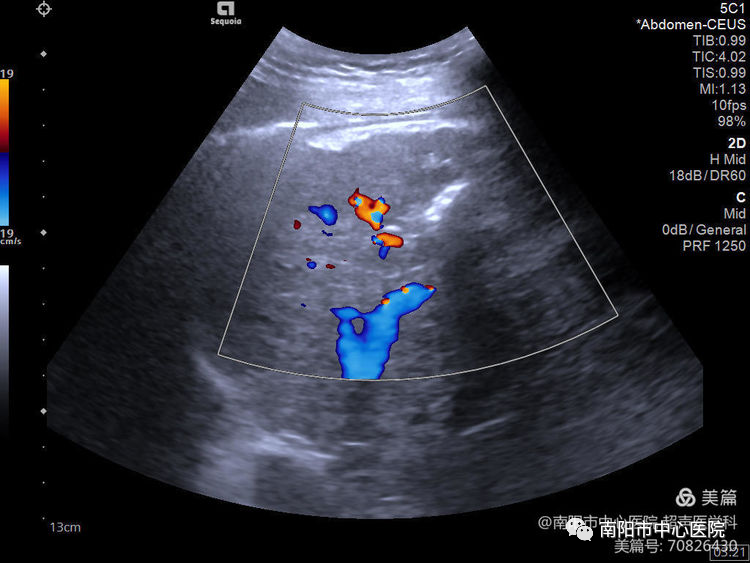

術(shù)前常規(guī)超聲探查,腫瘤位于肝S8,大小約31*20*18mm,周邊可見肝中靜脈、門脈右前支包繞。

術(shù)前行超聲造影,可見腫瘤動脈期呈高增強,形態(tài)欠規(guī)則。